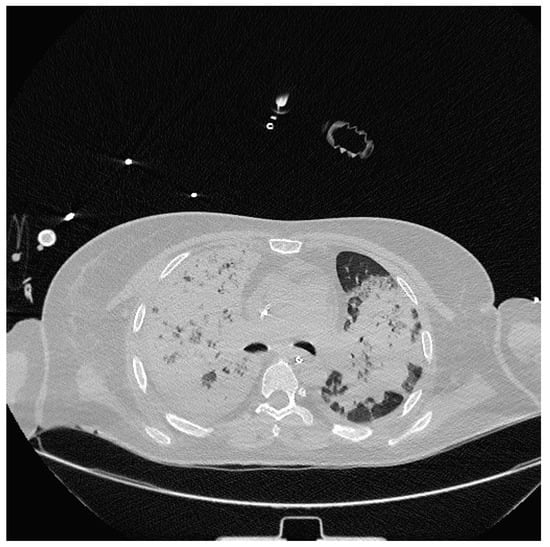

Severe hypoxia despite supplemental oxygen and respiratory distress required orotracheal intubation and mechanical ventilation in the emergency room. A chest CT scan was then performed, which showed extensive consolidation of the right lung and subtotal consolidation of the left lung (Figure 2).

Figure 2.

Chest CT showing extensive parenchymal thickening of the entire right lung and subtotal consolidation of the left lung.